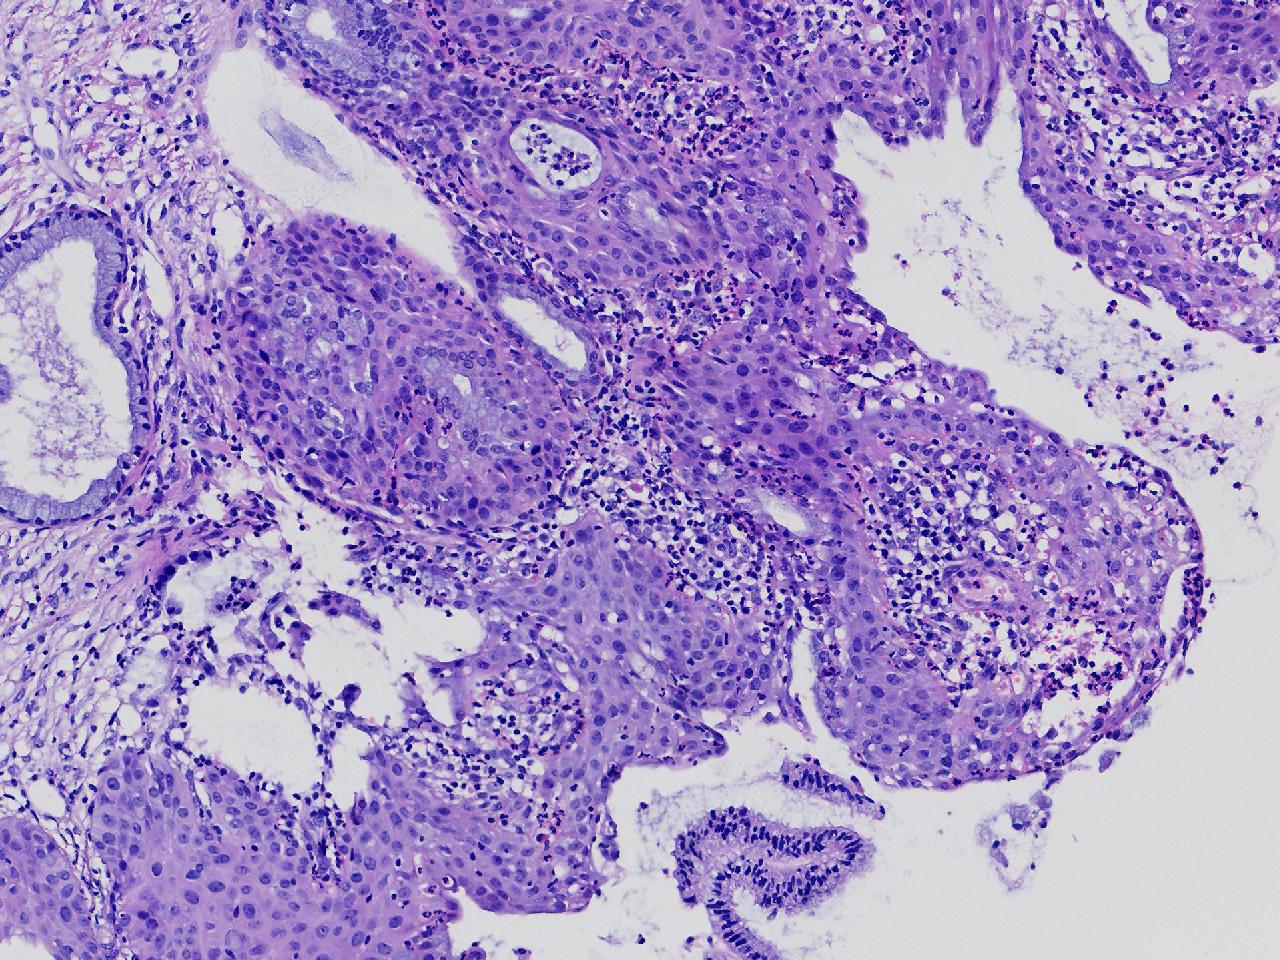

宫颈活检,有没有CIN?

女

36岁

宫颈病变

TCT示:ASC-US,HPV不详。

宫颈活检

图3

慢性宫颈炎伴腺上皮鳞化。

(宫颈活检组织) 慢性炎,储备细胞增生伴鳞化。